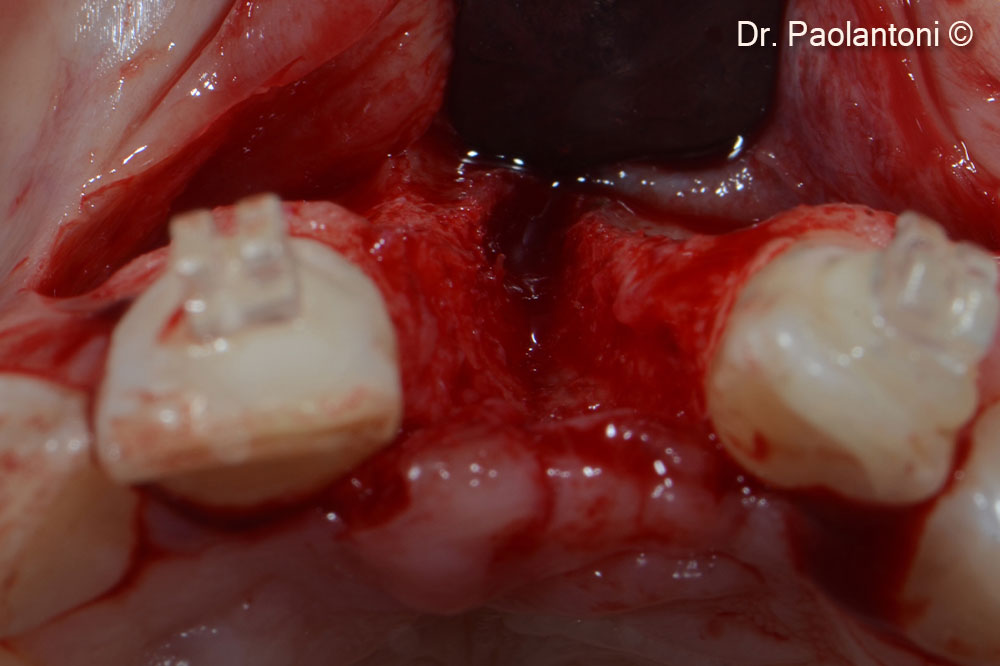

Horizontal bone defect after flap elevation